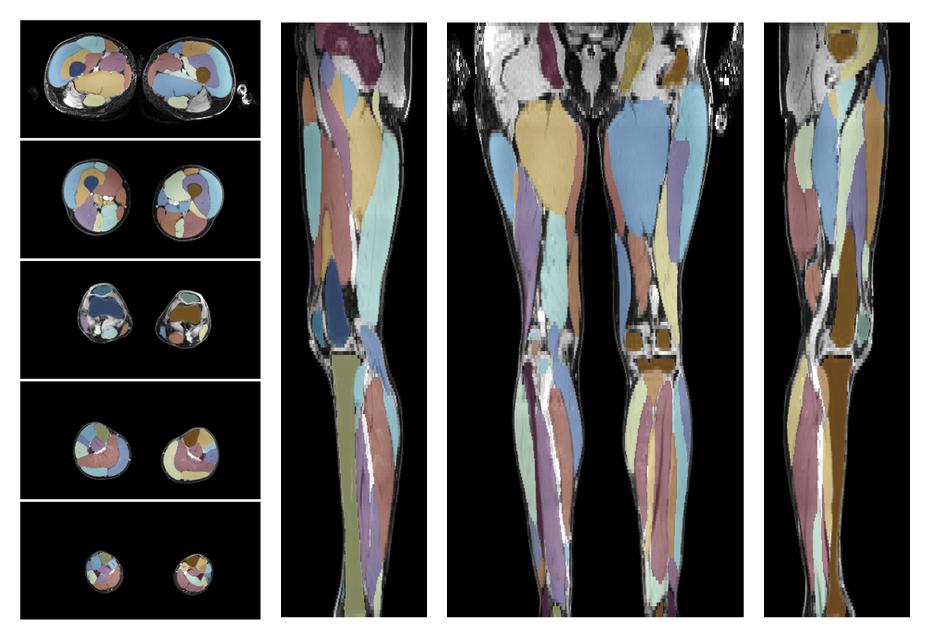

Muscle segmentation

Convolution neural network based (UNET) fiber automated muscle segmentation, for information look here».

• Automated muscle and bone segmentation.

Overlay of automated muscle segmentation labels on dixon water image.